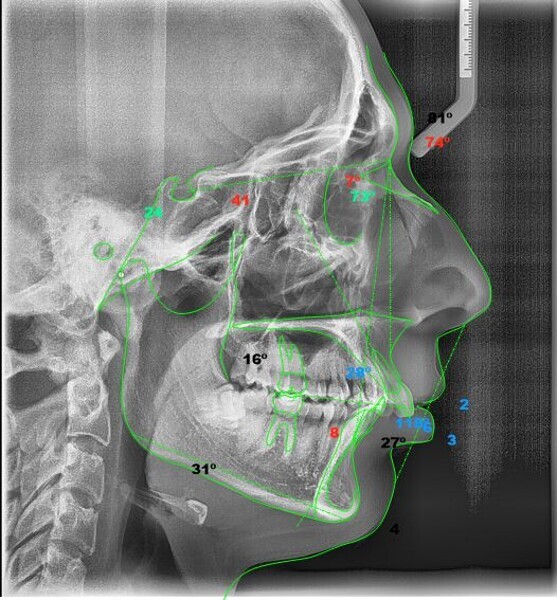

The pre- and post-treatment cephalometric tracings were also superimposed, obtaining the following results (Fig. 24):

• Area 1: Slightly closed facial axis due to mandibular antero-rotation, because of having placed a Class II CMA distaliser.

• Area 2: Molar distalisation as a result of the procedures that were used and protrusion of Point A due to the action of retroclining the central incisor.

• Area 3: Proclination of the mandibular incisor due to the Class II elastics.

• Area 4: Retroclination of the maxillary incisor.

• Area 5: Decreased lower lip protrusion.

Fig. 24: Superimposed tracings, black corresponding to the pretreatment tracing and red to the post-treatment tracing.

Four years after this case had been completed, the patient came for a review, and both radiographic and photographic records were taken to evaluate any changes that may have occurred over this retention period (Figs. 26–30). Cephalometric analysis was performed again and the results compared with the immediate post-treatment results (Table 2).

The radiographic equipment used on this occasion was not the same as we had used before, so the results obtained should not be considered totally accurate. Despite this setback, the patient’s status remained significantly better than at the beginning of treatment, since the patient still had a Class I occlusion, his profile was harmonious, and most notably, he was still satisfied with the results.